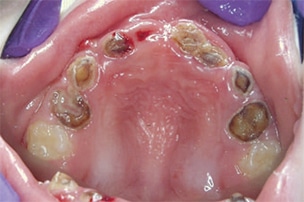

Severe ECC (S-ECC) is defined as any sign of smooth-surface caries in children younger than age 3. Additionally, in children ages 3 through 5, one or more dmf surfaces in primary maxillary anterior teeth, or a dmf score of ≥ 4 (age 3), ≥ 5 (age 4), or ≥ 6 (age 5) surfaces also constitutes S-ECC.3 The typical early sign of ECC is the crescent shaped white spot lesion at the gingival margin (Figure 1 to Figure 4).

According to the Agency for Healthcare Research and Quality sponsored United States Medical Expenditures Panel Survey, the average dental expense in 2004 for children younger than 6 was $186 per child.7 The total cost associated with care is estimated at slightly more than $1 billion annually.7 Treating ECC often requires extensive restorative treatment or the extraction of primary teeth. In addition to the expenses of dental restorations, general anesthesia or sedation may be required if children lack the ability to cope with dental procedures. General anesthesia to facilitate dental treatment may add anywhere between $1,500 and $6,000 to the cost of dental care.8 ECC also may contribute to other health problems, such as weight loss, however, the evidence for this is inconsistent.9 Sadly, ECC continues to be the most common chronic disease in children.10